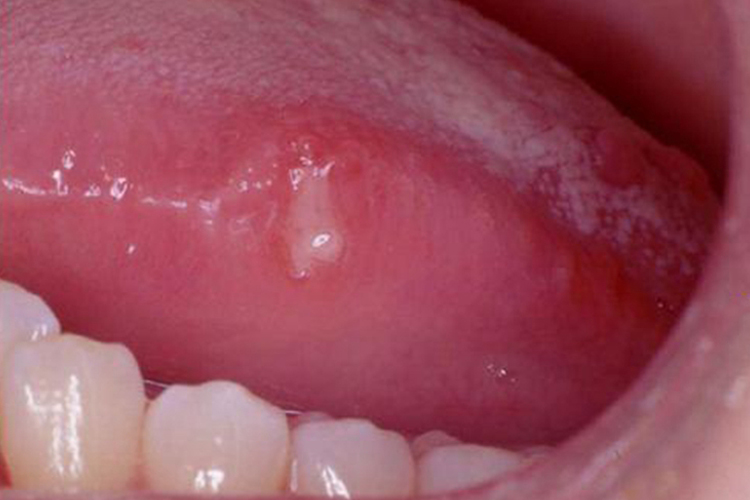

舌部的轻型阿弗他溃疡初起为局限性的黏膜充血水肿,呈粟粒状红点,灼痛明显;继而形成圆形或椭圆形的浅表溃疡,直径约5-10mm;数日后溃疡面逐渐生长出肉芽组织并自行愈合,不会留下瘢痕。溃疡可单发,也可同时出现3-5个,最多不超过10个,呈散在分布,病情可复发,一般无明显的全身症状。

Riga Fede溃疡专指婴儿舌系带由于创伤而产生的增殖性溃疡,多见于舌系带短的婴儿。开始时在舌系带处充血、发红、肿胀,久之上皮破溃即形成溃疡。由于持续不断的摩擦,溃疡面逐渐扩大,长久得不到治疗即可转变为增殖性、炎症性、肉芽肿性溃疡。